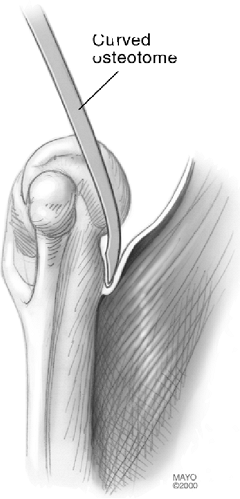

brachialis muscle is released from the anterior cortex of the humerus

with a curved elevator to accommodate the flange (Fig. 18-18).

![]() |

|

Figure 18-18. The anterior capsule and brachialis muscle insertion are released from the anterior humeral cortex with a curved osteotome.